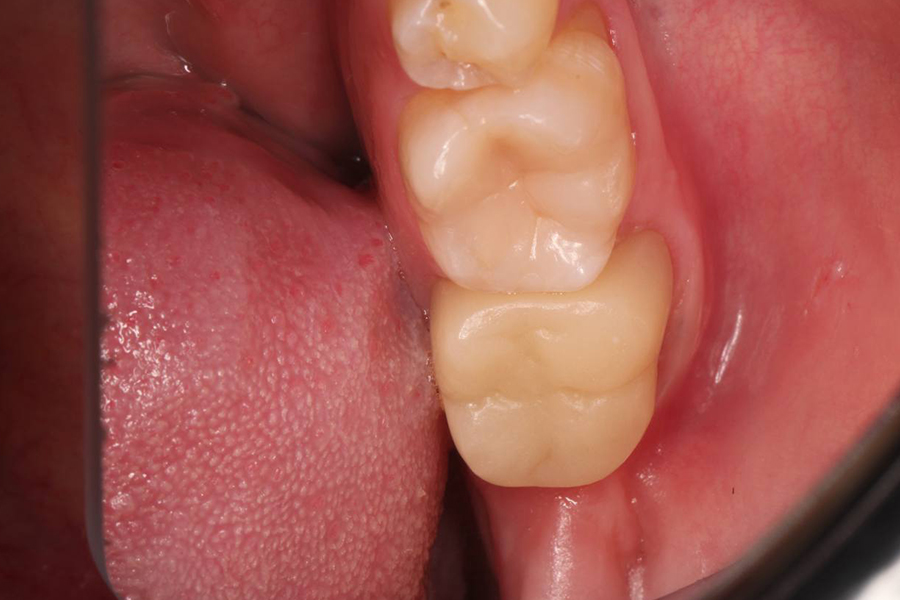

Результат

По результатам КЛКТ мы наблюдаем положительную динамику, уменьшение очага деструкции костной ткани